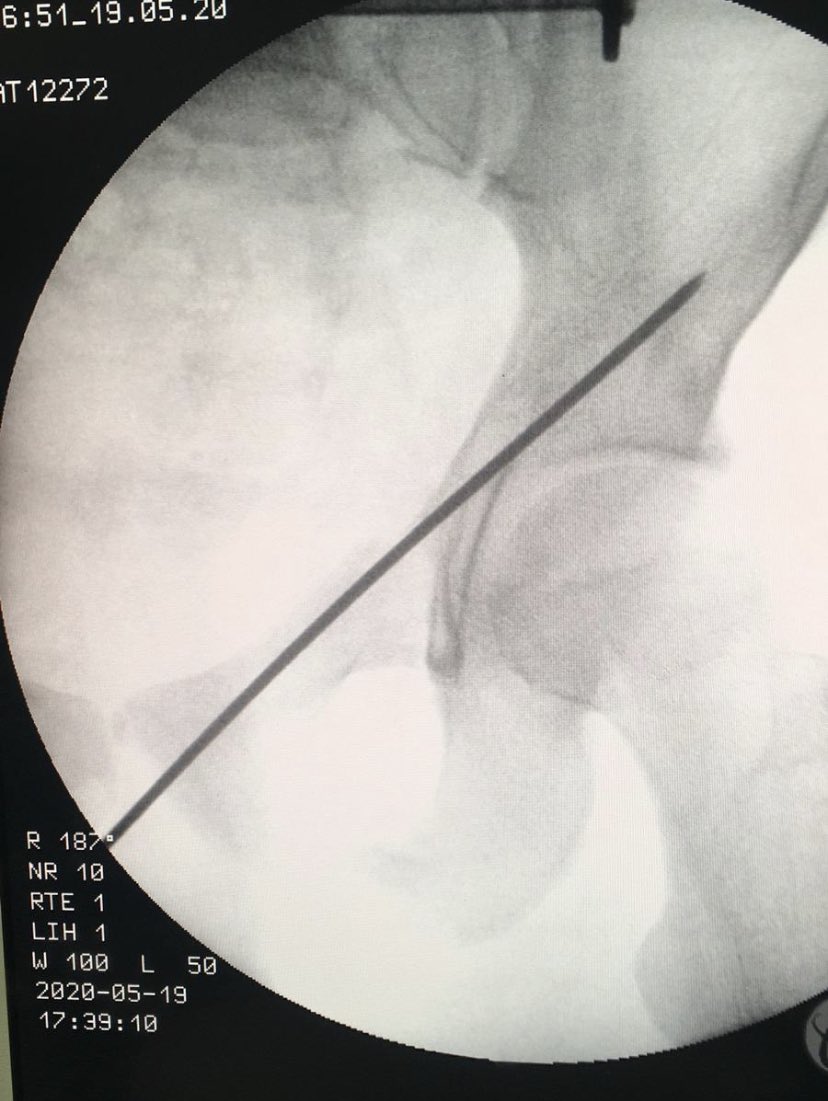

Percutaneous acetabular fixation

Dr. Diego López tweet mediaDr. Diego López tweet mediaDr. Diego López tweet media